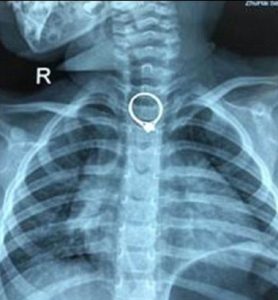

L'anello nell'esofago della bambina

La vicenda la racconta il Daily Mail: la figlioletta della signora Deng aveva inghiottito il prezioso. I medici del Zhuhai Secondary Hospital, nella provincia del Guangdong, nel pomeriggio del 23 marzo hanno rimosso con successo l’anello di 2,35 × 2,05 centimetri dall’esofago (la parte del sistema digestivo che collega la bocca allo stomaco).

“Abbiamo trovato l’anello bloccato nella prima sezione dell’esofago. L’anello ha alcuni spigoli vivi e sarebbe potuto essere pericoloso se Beibei avesse continuato a piangere perché l’anello avrebbe potuto essere spinto verso il basso allo stomaco”, ha spiegato la dottoressa Chen Gang, specialista in otorinolaringoiatria.